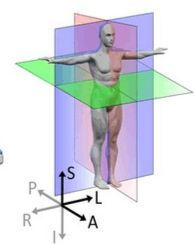

首先要明确一下和人体对应的方向,其中三个窗口对应三个切面,对应关系如下图所示,按照字母索引即可。例如,左上图对应R-A-L-P这个面,是从脚底往头部方向看的切面(即z方向),另外两张类似。

红色切面为矢状面,紫色切面为冠状面,绿色切面为横断面

也可以同时将分割结果导入,对比观察。

对于标注不太严谨的地方也可以精细化修改。当然公开集的话,绝大多数都挺好的。自己标注也是类似。(如果显示不太清晰,对比度太低,需要在软件中调节窗宽和窗位)